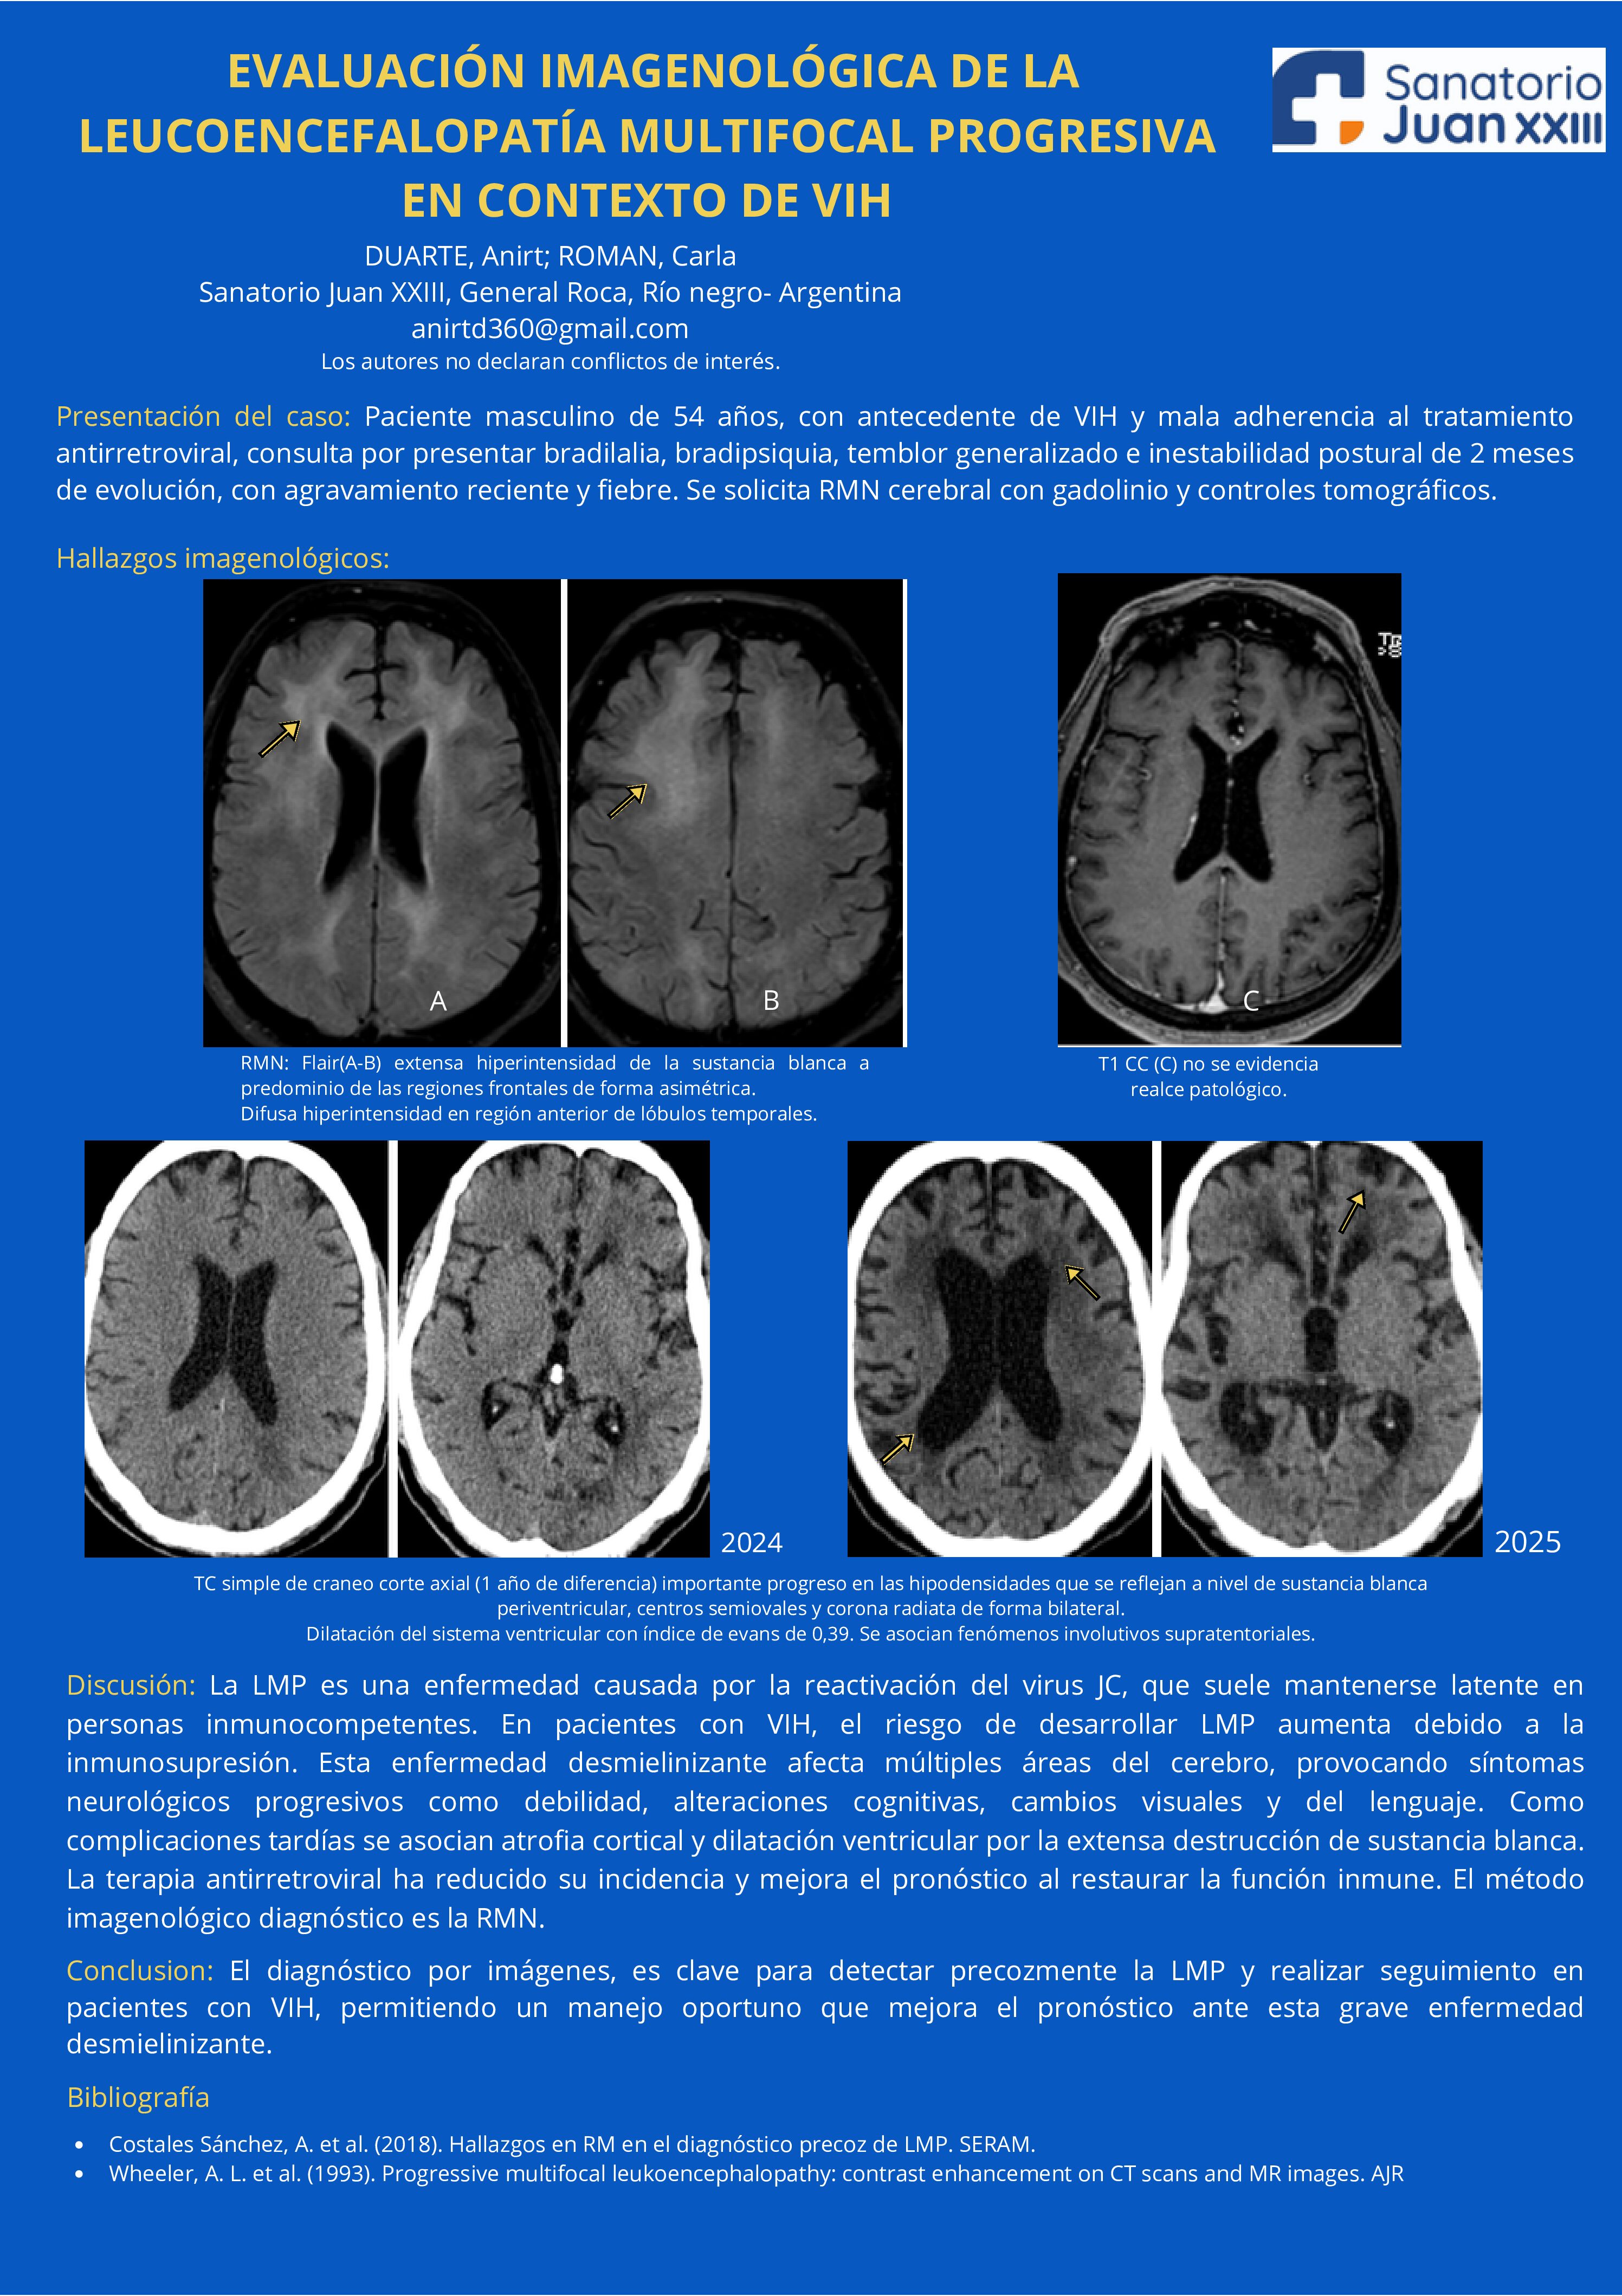

EVALUACIÓN IMAGENOLÓGICA DE LA LEUCOENCEFALOPATÍA MULTIFOCAL PROGRESIVA EN CONTEXTO DE VIH

10/07/2025